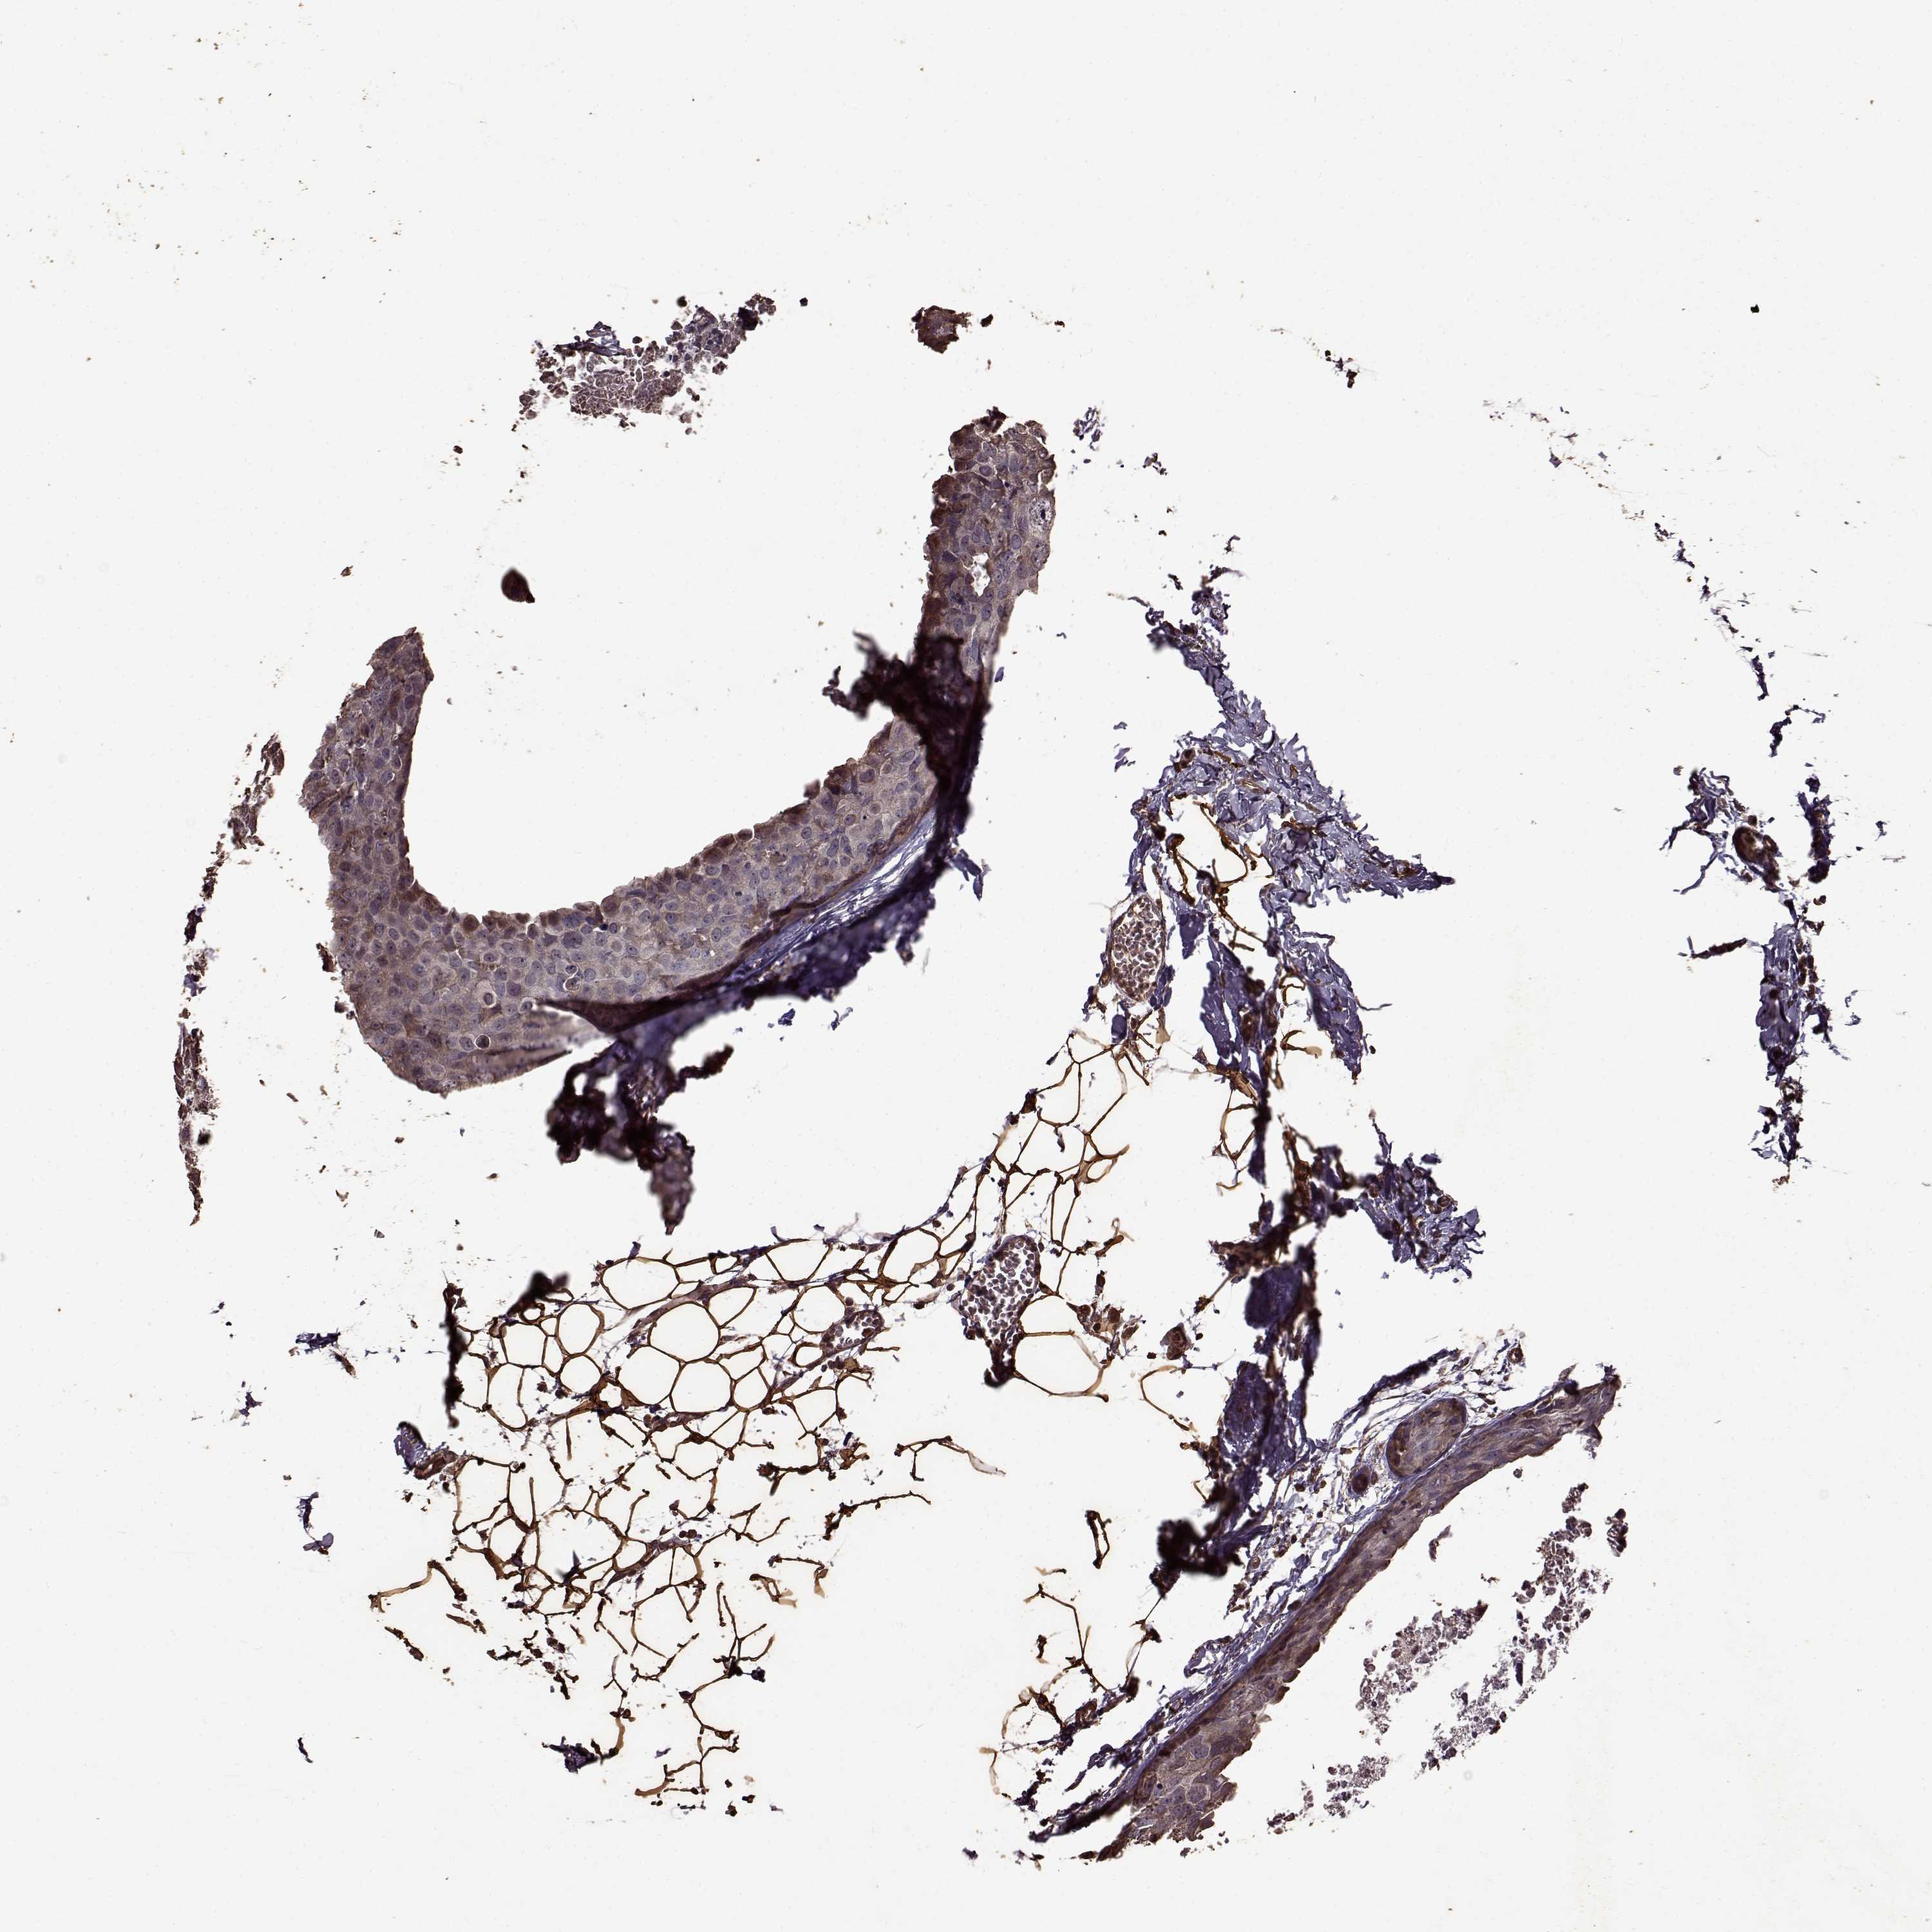

CANCER BREAST CANCER Show tissue menu

BRCA TCGA BRCA VALIDATION PROTEIN EXPRESSION